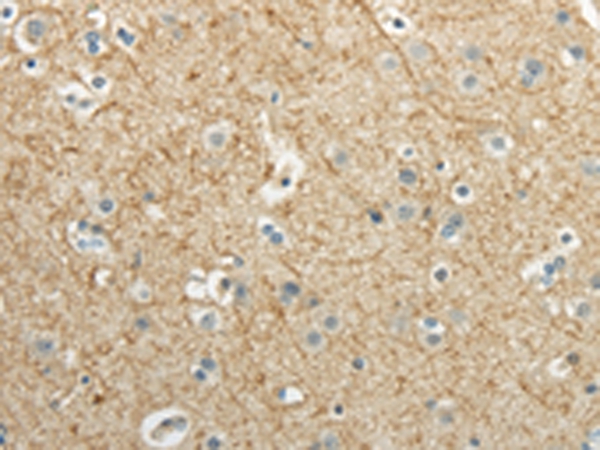

分类: 科研抗体货号: P43470别名: WEE1A; WEE1hu应用: WB,IHC反应种属: Human,Mouse,Rat